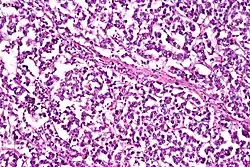

| Micrograph of a dysgerminoma, H&E stain. | |

They are exceptionally associated with hypercalcemia. On gross examination, dysgerminomas present with a smooth, bosselated (knobby) external surface, and are soft, fleshy and either cream-coloured, gray, pink or tan when cut. Microscopic examination typically reveals uniform cells that resemble primordial germ cells. Typically, the stroma contains lymphocytes and about 20% of patients have sarcoid-like granulomas. Metastases are most often present in the lymph nodes.